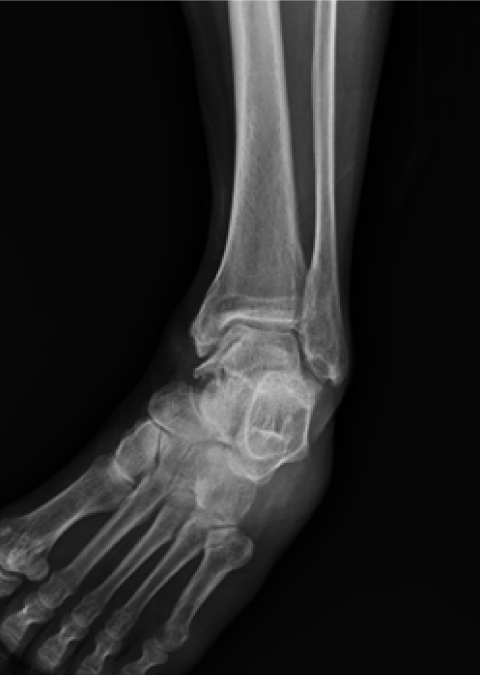

발목관절염 수술 전

2020.06.26

발목관절염 수술 후

2022.10.14

ㆍ환자 동의를 받은 자료이며, 이미지 사진은 실물과 다를 수 있습니다.

ㆍ모든 자료는 새움병원 자료입니다.